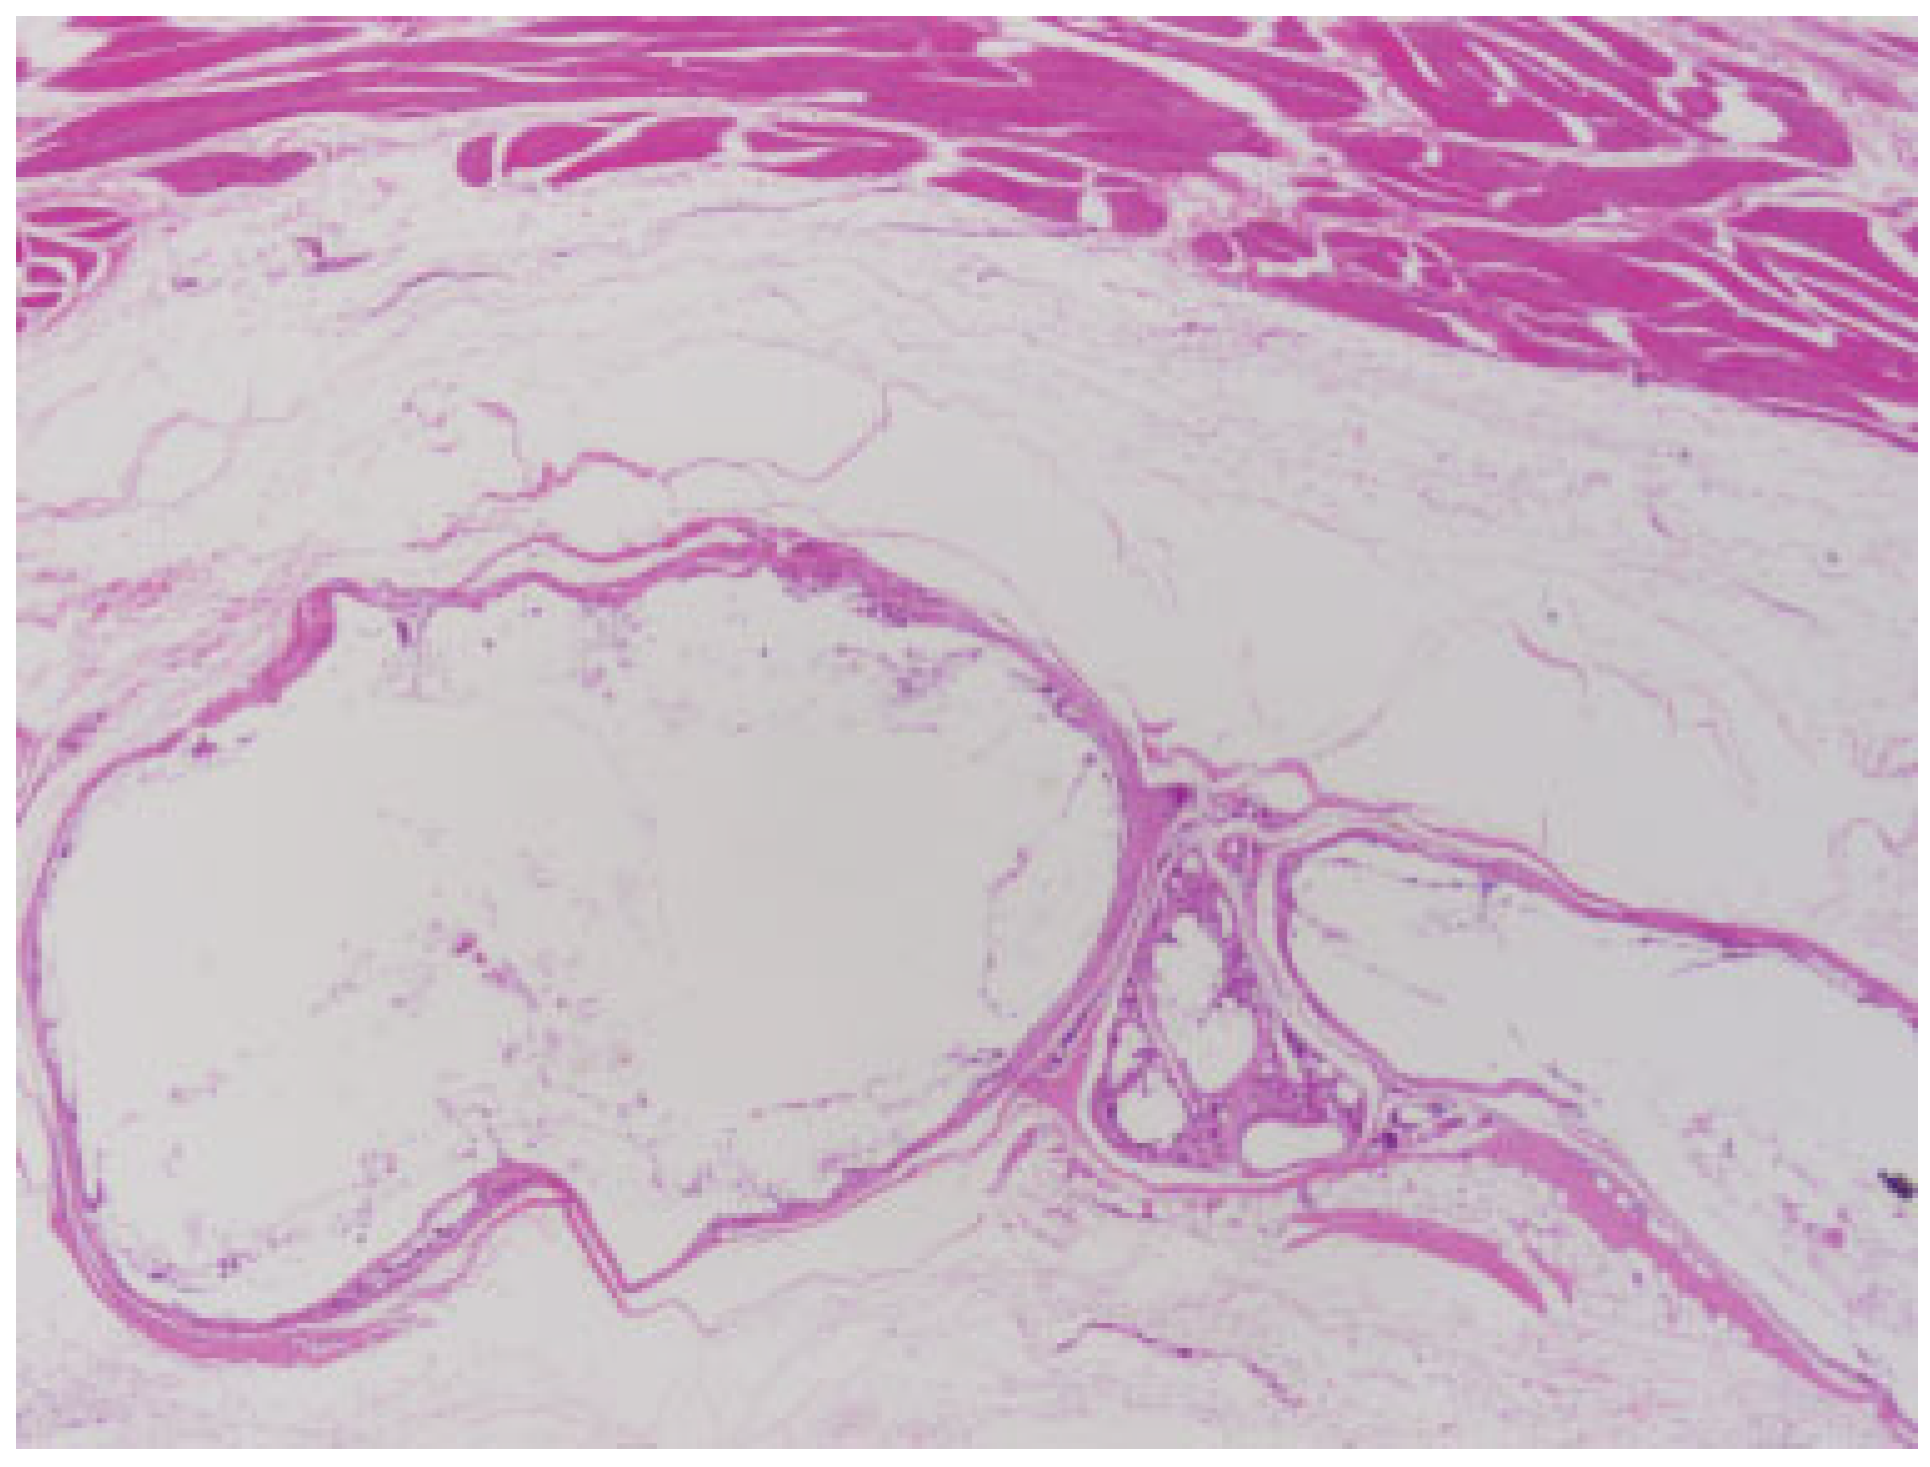

Figure 2.

Poly(D/L)lactide acid plate at 3 months postimplantation. The implant demonstrated fragmentation and giant cell infiltration into the implant. Surrounding loose connective tissue is normal in appearance without evidence of inflammation, cellulitis, or abscess formation. (light microscopy, hematoxylin and eosin stain, original magnification ×40).

Figure 3.

Poly(D/L)lactide acid plate at 3 months postimplantation, demonstrated small encapsulated implant fragments surrounding by giant cells, indicating active resorption. Note that foreign-body reaction is limited entirely within the implant capsule. (light microscopy, hematoxylin and eosin stain, original magnification ×400).